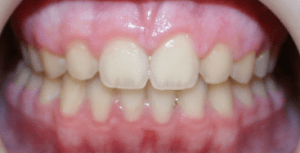

Before

After

Depending upon the situation, space can be closed with braces or opened for tooth replacement. A dental implant or bridge are restorative options if a space is created.